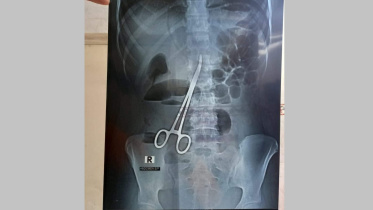

পেটে কাঁচি রেখে সেলাই: কারও দায় পায়নি তদন্ত কমিটি

ফরিদপুর বঙ্গবন্ধু শেখ মুজিব মেডিকেল কলেজ হাসপাতালে তরুণীর পেটে অস্ত্রোপচারের পর কাঁচি রেখে সেলাই করার ঘটনায় প্রতিবেদন জমা দিয়েছে তদন্ত কমিটি।

পেটে কাঁচি রেখেই সেলাই, ৬৪৩ দিন পর অপসারণ

ফরিদপুরে বঙ্গবন্ধু শেখ মুজিব মেডিকেল কলেজ হাসপাতালে এক তরুণীর পেটে অস্ত্রোপচারের সময় চিকিৎসকের রেখে দেওয়া একটি কাঁচি ৬৪৩ দিন পর আবার অস্ত্রোপচার করে বের করা হয়েছে।